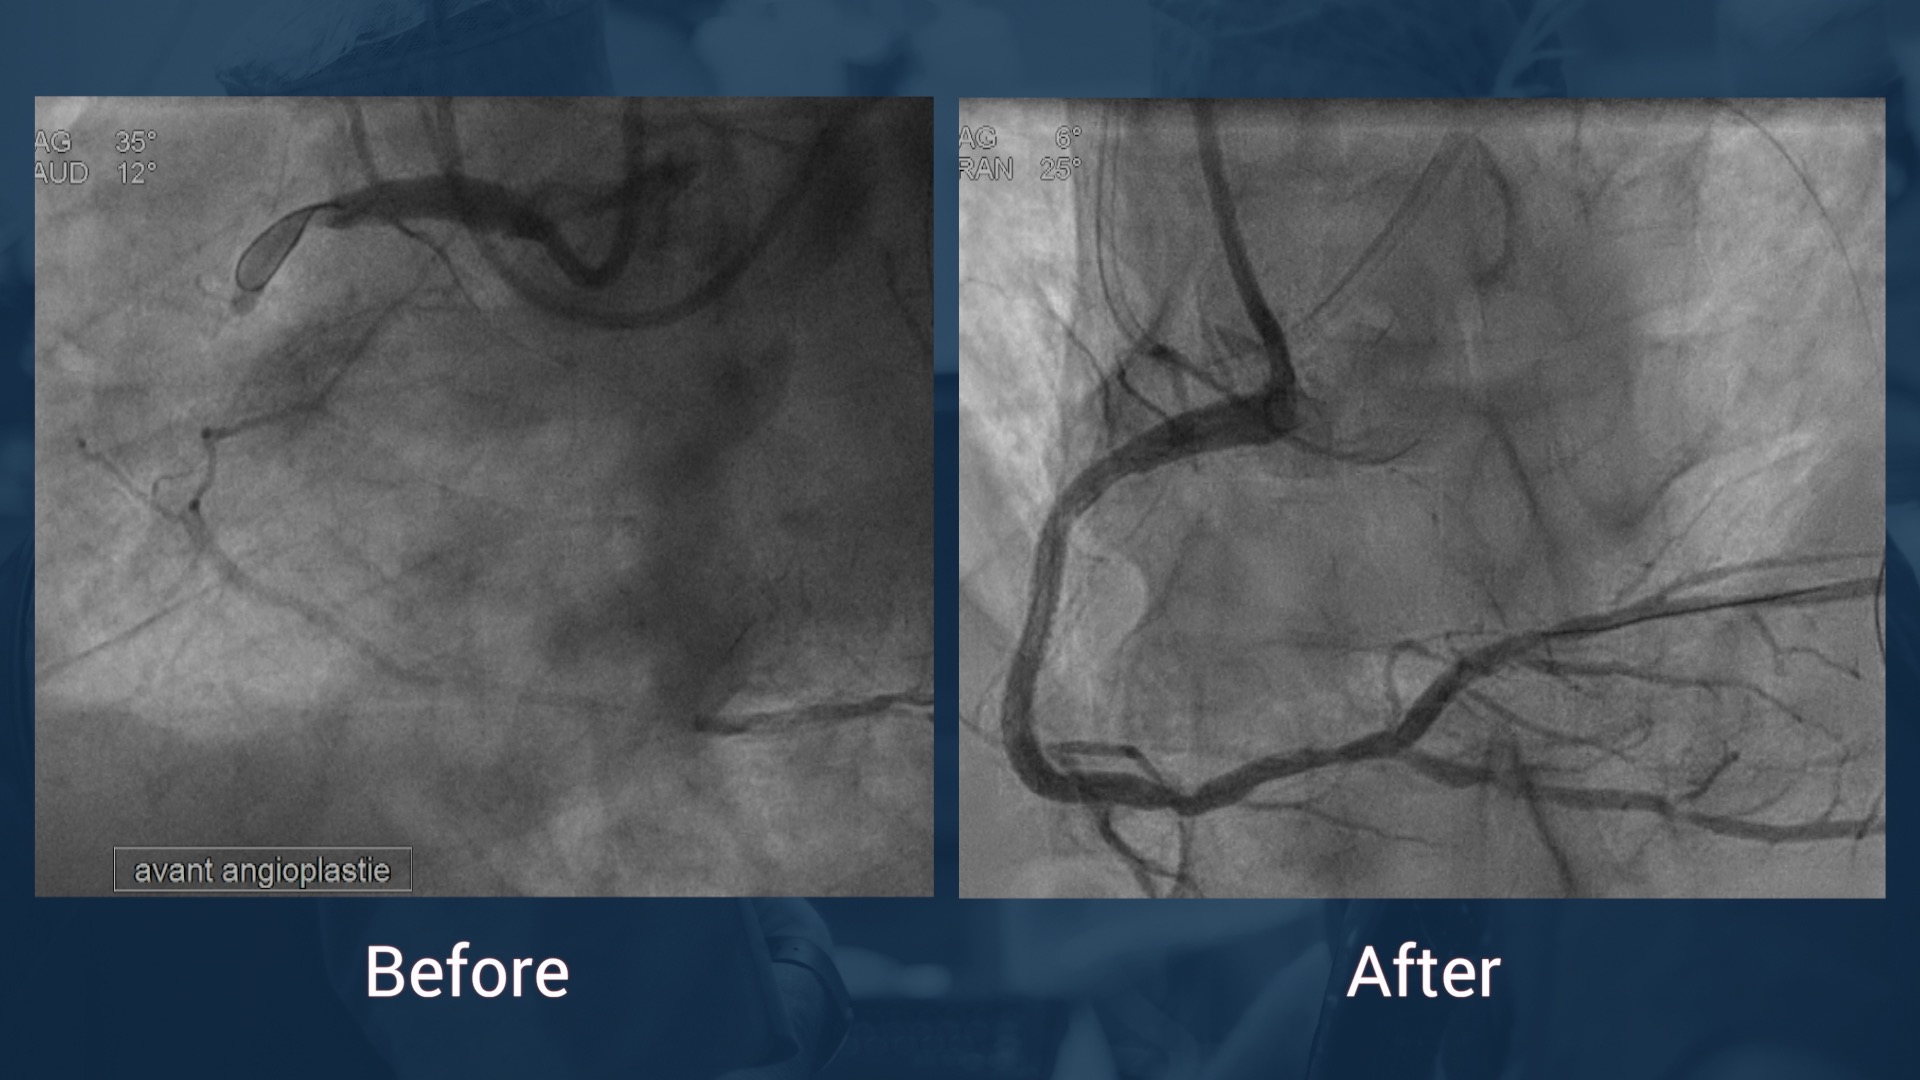

RCA:  CTO of proximal segment with ipsilateral epicardial  collaterals to the PL-branch